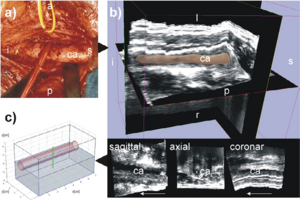

Publication: Sci Rep. 2015 Dec 14;5:18156. PMID: 26657471 | PDF Authors: Hagen CK, Maghsoudlou P, Totonelli G, Diemoz PC, Endrizzi M, Rigon L3, Menk RH, Arfelli F, Dreossi D, Brun E, Coan P, Bravin A, De Coppi P, Olivo A. Institution: University College London, Department of Medical Physics and Biomedical Engineering, London, UK. Background/Purpose: Acellular scaffolds obtained via decellularization are a key instrument in regenerative medicine both per se and to drive the development of future-generation synthetic scaffolds that could become available off-the-shelf. In this framework, imaging is key to the understanding of the scaffolds' internal structure as well as their interaction with cells and other organs, including ideally post-implantation. Scaffolds of a wide range of intricate organs (esophagus, lung, liver and small intestine) were imaged with x-ray phase contrast computed tomography (PC-CT). Image quality was sufficiently high to visualize scaffold microarchitecture and to detect major anatomical features, such as the esophageal mucosal-submucosal separation, pulmonary alveoli and intestinal villi. These results are a long-sought step for the field of regenerative medicine; until now, histology and scanning electron microscopy have been the gold standard to study the scaffold structure. However, they are both destructive: hence, they are not suitable for imaging scaffolds prior to transplantation, and have no prospect for post-transplantation use. PC-CT, on the other hand, is non-destructive, 3D and fully quantitative. Importantly, not only do we demonstrate achievement of high image quality at two different synchrotron facilities, but also with commercial x-ray equipment, which makes the method available to any research laboratory. Funding:

Images acquired with synchrotron-based PC-CT showing a rat small intestine that was decellularized via DET: (a) transverse cross section, (b) three-dimensional view. All scale bars represent 500 μm. Images were processed using the ESRF in-house software PyHST, and analyzed and displayed with ImageJ31 and 3D Slicer. |